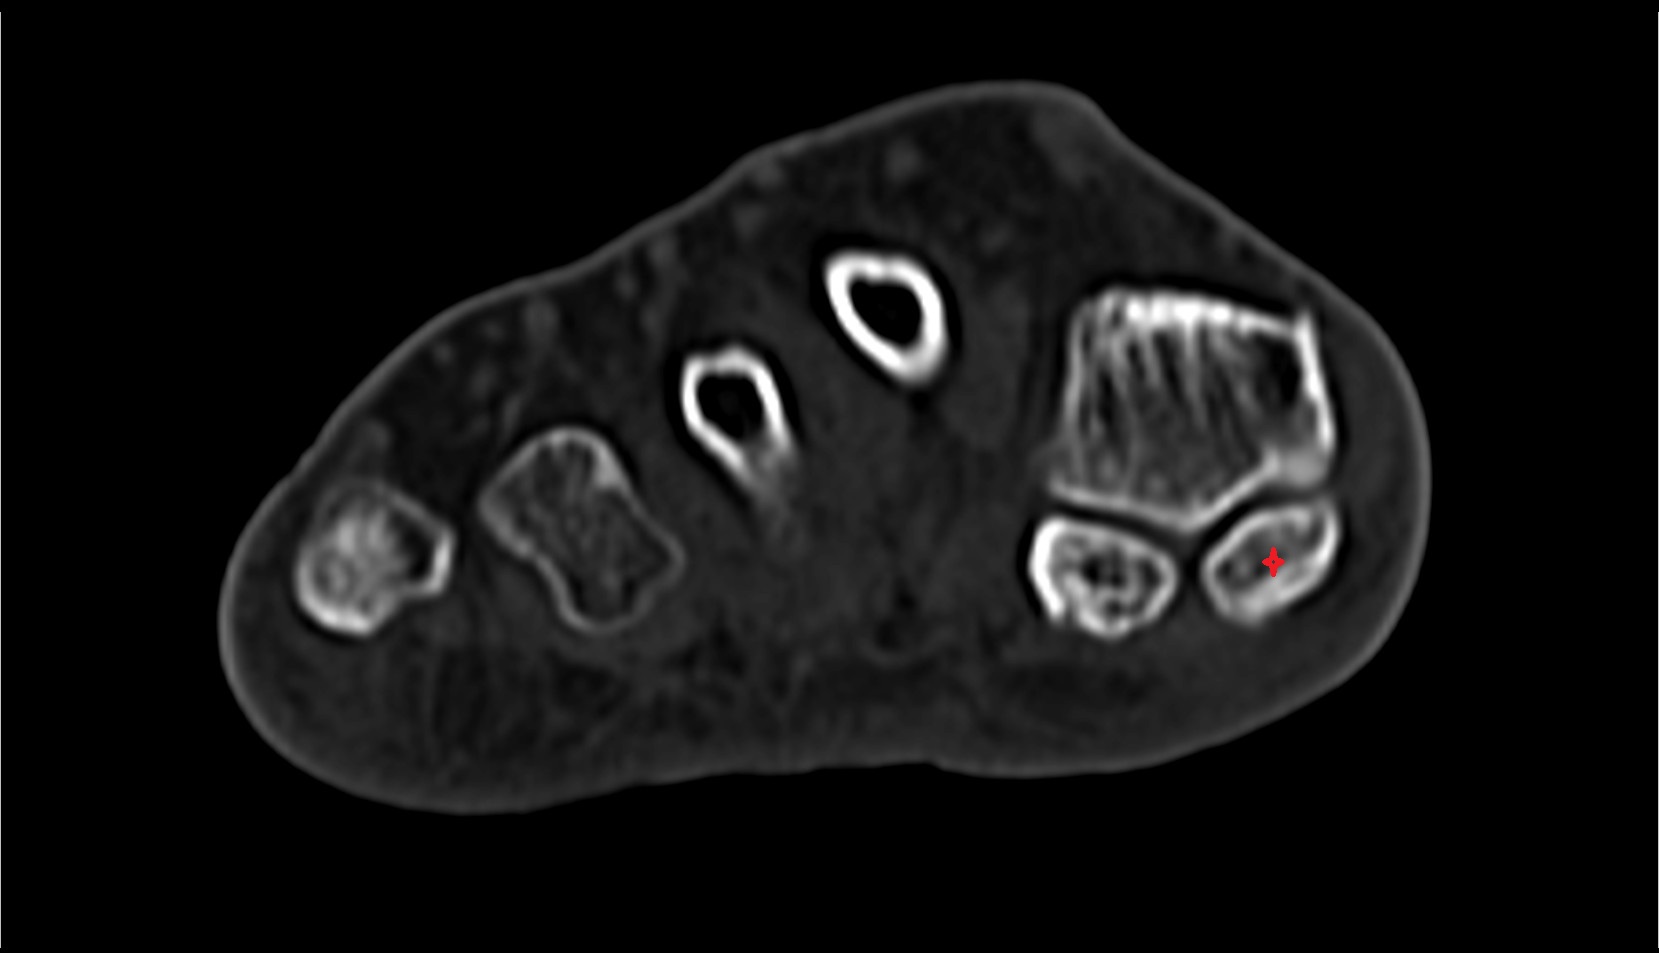

- Sesamoid bone of great toe

- Lateral sesamoid bone

- Medial sesamoid bone

- First metatarsal bone

- Metatarsophalangeal joints

- Flexor hallucis brevis muscle

- Lateral head of flexor hallucis brevis muscle

- Medial head of flexor hallucis brevis muscle